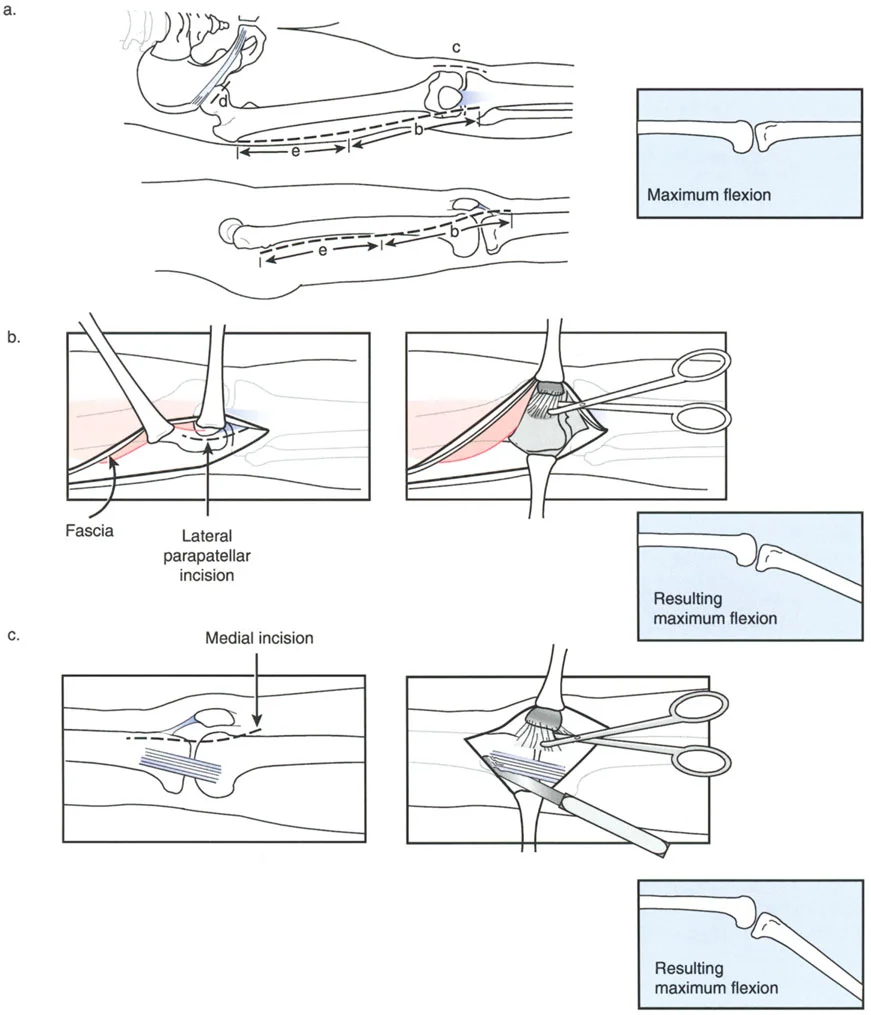

توضح الصورة المحاور التشريحية والزوايا الطبيعية لعظم الفخذ والظنبوب، والتي تُعد أساساً لفهم تشوهات الركبة السهمية.

يتطلب التخطيط السليم تحديد خطوط العظام الطويلة وحساب قمة التشوه بدقة. وكما هو الحال في مبادئ محاذاة المحور، فإن تحديد خطوط منتصف العظم بالنسبة لخطوط توجيه المفصل هو الخطوة الأولى في تحديد مركز دوران الانحراف (CORA)، وهو النقطة التي يجب أن يتم عندها قطع العظم لتصحيح التشوه.

التقوس الأمامي (Procurvatum) في الفخذ

ينتج التقوس الأمامي في الجزء البعيد من عظم الفخذ عادة عن فقدان تعويضي في قدرة الركبة على التمدد الكامل، أو اندفاع تقوسي ثانوي أثناء مرحلة الوقوف في المشي. نظراً لأن الجزء البعيد من عظم الفخذ ينحني للأمام، فإن خط المفصل يميل، مما يجبر عظم الظنبوب على فرط الاستقامة ببساطة للسماح للمريض بالوقوف بشكل مستقيم مع قدم مستوية.

عند تصحيح تشوه التقوس الأمامي، يجب على الجراح حساب مركز دوران الانحراف (CORA) بعناية. غالباً ما يكون التشوه قريباً جداً من المفصل، مما يجعل تثبيت العظم بعد القطع أمراً صعباً.

دور الحدبة الظنبوبية في التخطيط لقطع العظم

عند التخطيط لقطع العظم لتصحيح التقوس الخلفي في الظنبوب، فإن موقع القطع العظمي بالنسبة للحدبة الظنبوبية هو القرار الأكثر أهمية الذي سيتخذه الجراح. فالنتائج الميكانيكية الحيوية لهذا الاختيار تحدد ما إذا كان خلع الركبة الجزئي سيتم تقليله أو تفاقمه بشكل كارثي.

قطع العظم فوق الحدبة الظنبوبية (النهج المفضل)

عندما يوجد تشوه تقوس خلفي مع وجود الحدبة الظنبوبية بالقرب من خط المفصل، فإن قطع العظم على شكل إسفين فتح فوق الحدبة الظنبوبية يكون مفيداً للغاية ويمثل المعيار الذهبي في مبادئ بالي لإعادة البناء.

- آلية العمل: يؤدي فتح إسفين عند هذا المستوى المحدد إلى تصحيح محاذاة العظم التقوسية، واستعادة زاوية PPTA الطبيعية (81-84 درجة) مباشرة.

- تقليل المفصل غير المباشر: نظراً لأن الحدبة الظنبوبية تبقى على الجزء البعيد من قطع العظم، فإن فتح الإسفين للأمام يسحب وتر الرضفة جسدياً. يعمل هذا الشد كحزام تقليل داخلي، يسحب كامل ساق الظنبوب وهضبة الظنبوب للأمام، وبالتالي يقلل بشكل غير مباشر الخلع الجزئي الخلفي للمفصل الظنبوبي الفخذي.

- منع انخفاض الرضفة: قد يفترض المرء أن سحب الحدبة الظنبوبية للأسفل سيسبب انخفاضاً في الرضفة. ومع ذلك، نظراً لأن كامل الظنبوب يتحرك للأمام وتتغير زاوية المفصل، فإن انخفاض الرضفة الثانوي لا يحدث. يتم الحفاظ على المسافة النسبية بين الرضفة وخط المفصل.

- نقل الشظية: يمكن أن يساعد نقل الشظية للأسفل أيضاً في تقليل الخلع الجزئي الخلفي. نظراً لأن الرباط الجانبي الوحشي (LCL) موجه في اتجاه أمامي خلفي، فإن سحب الشظية للأسفل يشد الرباط الجانبي الوحشي، مما يساعد في الترجمة الأمامية للظنبوب.

مخاطر قطع العظم تحت الحدبة الظنبوبية

على العكس من ذلك، إذا تم إجراء قطع عظمي على شكل إسفين فتح أسفل الحدبة الظنبوبية، فإن الجراح يخلق كارثة ميكانيكية حيوية.

بينما قد يتم تصحيح التقوس الخلفي في ساق الظنبوب إشعاعياً، فإن الخلع الجزئي الخلفي للمفصل يترك دون علاج تماماً. نظراً لأن الحدبة الظنبوبية تقع على الجزء القريب، فإن وتر الرضفة لا يتم شده. يبقى المفصل مخلوعاً جزئياً، مما يؤدي إلى عدم استقرار مستمر، وتآكل سريع للغضروف، وآلام غير محلولة.

تقنية قطع العظم على شكل حرف L

لتصحيح هذا التشوه المعقد، متعدد المستويات داخل المفصل والميتافيزي، فإن قطع العظم المستعرض القياسي غير كافٍ. تُعد تقنية قطع العظم على شكل حرف L هي الإجراء المفضل.

- التصميم: يتم تصميم قطع العظم بدقة لفصل الكتلة المفصلية المنخفضة عن الحدبة الأمامية. يمتد الجزء العمودي من "L" خلف الحدبة، بينما يمتد الجزء الأفقي أسفل الهضبة المنخفضة.

- التنفيذ: يسمح هذا للجراح برفع الكتلة المفصلية المنخفضة للأعلى وإمالتها للأمام، مع إعادة وضع الحدبة الظنبوبية إلى موقعها التشريحي بالنسبة لخط المفصل في نفس الوقت.

- التثبيت: يتيح استخدام جهاز إليزاروف أو إطار دائري سداسي الأرجل تصحيحاً تدريجياً ومتحكماً للتقوس الخلفي. توفر الأسلاك الدقيقة تثبيتاً ممتازاً في الجزء المفصلي القريب الصغير.

- النتيجة: استعادة كاملة لزاوية PPTA، وتقليل تشريحي للمفصل الظنبوبي الفخذي، وتطبيع مستوى إدخال وتر الرضفة.